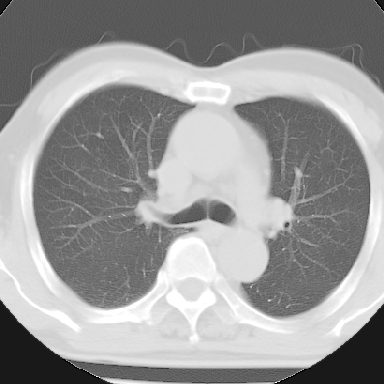

标题: CT8275:M 77 反复咳嗽咳痰10多年,慢性支气管炎请分析 [打印本页]

标题: CT8275:M 77 反复咳嗽咳痰10多年,慢性支气管炎请分析

m 77 反复咳嗽咳痰10多年,再发加重4天

纵隔窗呢?慢支炎肺气肿;余未见明显渗出及占位!

不支持慢性支气管炎,另外慢性支气管炎的诊断需结合临床病史才能诊断。

这份病例诊断慢支并气肿可能属过诊,首先慢支的临床诊断标准是严格的,应该弄清楚,其次ct表现是否符合该病表现,本例老年人ct肺窗表现应属正常,不要跟着临床跑。